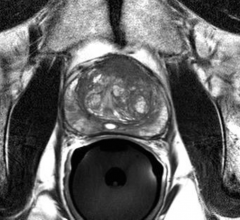

Prostate Cancer

News and new technology innovations concerning how imaging technology can help diagnose and treat prostate cancer can be found on this channel.